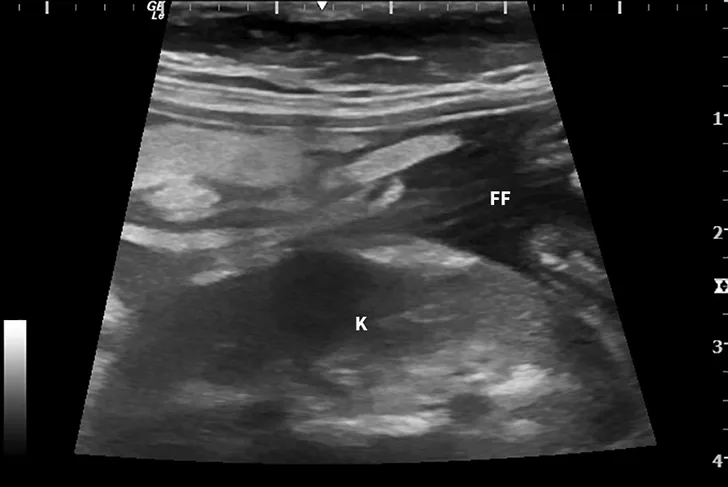

Dry FIP can manifest with organ dysfunction, uveitis, neurologic signs, fever, anemia, and/or lethargy and is caused by granulomas or immune complex deposition. Cats with wet FIP may have ascites or pleural effusion in addition to the aforementioned signs (Figure 1). Clinical presentation can vary from minor to life-threatening and involve almost any organ system.

Ultrasound image showing abdominal effusion in a cat with wet FIP. Anechoic fluid is present between organs, distending the abdomen. FF = free fluid; L = liver; S = spleen; K = kidney